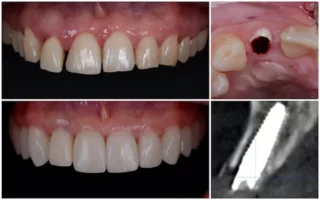

3. Az implantáció – a mesterséges gyökér beültetése

A beavatkozás helyi érzéstelenítésben történik, így a páciens semmit nem érez.

Az implantológus az előre meghatározott pozícióba beülteti a titánból készült műgyökeret az állcsontba.

Ez a kis csavar tölti be a foggyökér szerepét – stabil alapot ad a későbbi koronának vagy hídnak.

Az implantáció általában 30–60 percet vesz igénybe, teljesen fájdalommentesen.

5. A felépítmény és a végleges fogpótlás elkészítése

A gyógyulási idő leteltével az implantátumra egy apró felépítmény (csonkfej) kerül, erre rögzítjük a végleges koronát vagy hidat.

A SmileCenter fogtechnikusai digitális lenyomat alapján készítik el a pótlást, CAD/CAM technológiával – így az illeszkedés, a szín és a forma milliméter pontos.

A végeredmény természetes hatású, kényelmes és tartós.

Sok páciens el sem tudja különíteni az implantátumot a saját fogaitól – pontosan ez a cél.